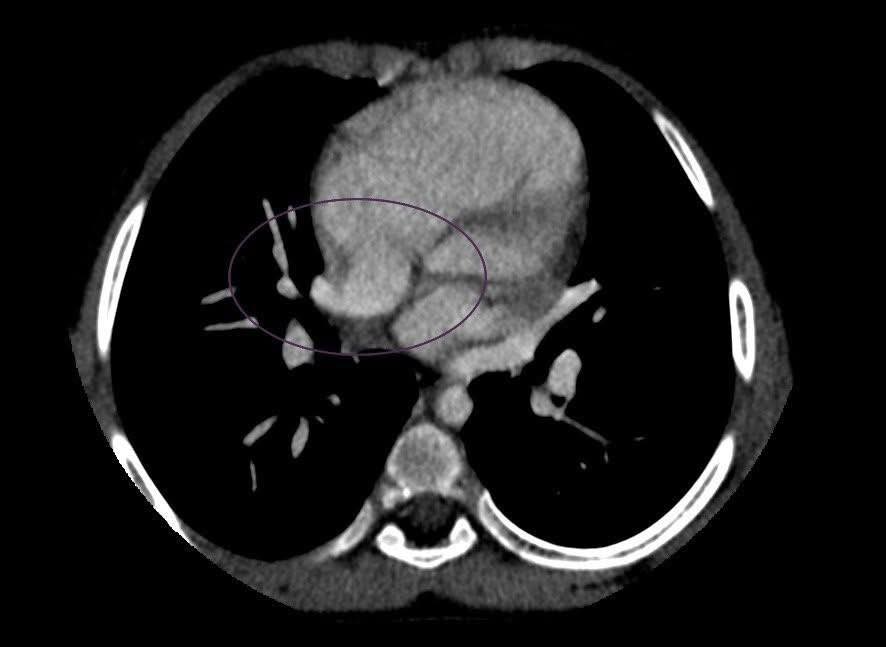

У Чернівецькій обласній дитячій лікарні вперше провели комп’ютерну томографію (КТ) серця 7-річній дитині, яка лікувалася від пневмонії. Після цього лікарі прийняли рішення про хірургічне втручання.

Для уточнення діагнозу до Чернівців прибули спеціалісти Інституту імені Миколи Амосова, які підтвердили підозру. Проте для остаточної верифікації діагнозу провели КТ серця з контрастуванням.

Обстеження виконали в обласній дитячій лікарні, після чого вирішили провести хірургічне лікування. Такі обстеження дітей у Чернівецькій області ще не проводили. Маленьких пацієнтів зазвичай скеровували до Києва.

Облрада зауважує: “КТ на місці є особливо важливим, адже не завжди стан дитини дозволяє безпечно її транспортувати”.